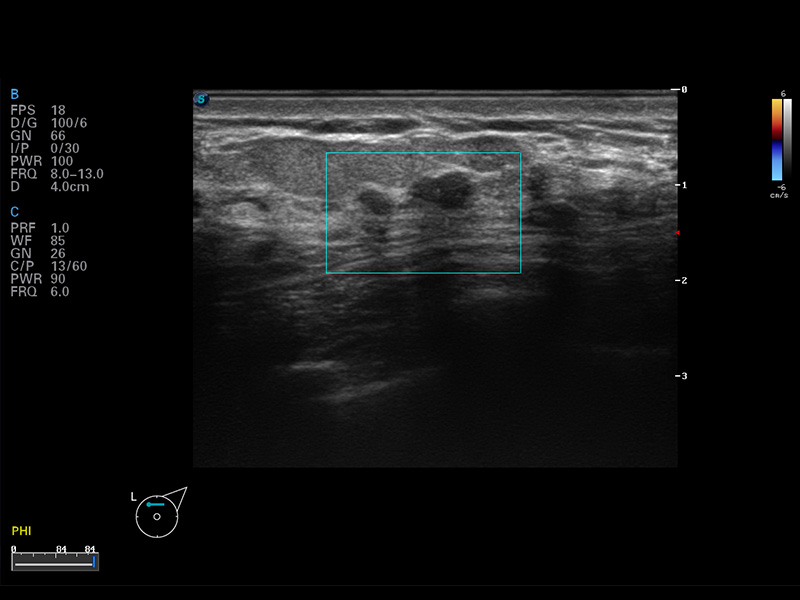

S8 EXP便携式彩色多普勒超声诊断仪是狗万官方网站研发的高端全身应用型便携彩超。高通道的VIS平台融合可视化(Visual)、智能化(Intelligent)和人性化(Smart)的特点,配以狗万官方网站自主研发生产的探头大家族,使您能够快速、准确的获得病人信息,提高工作效率的同时减轻疲劳。

空间复合成像